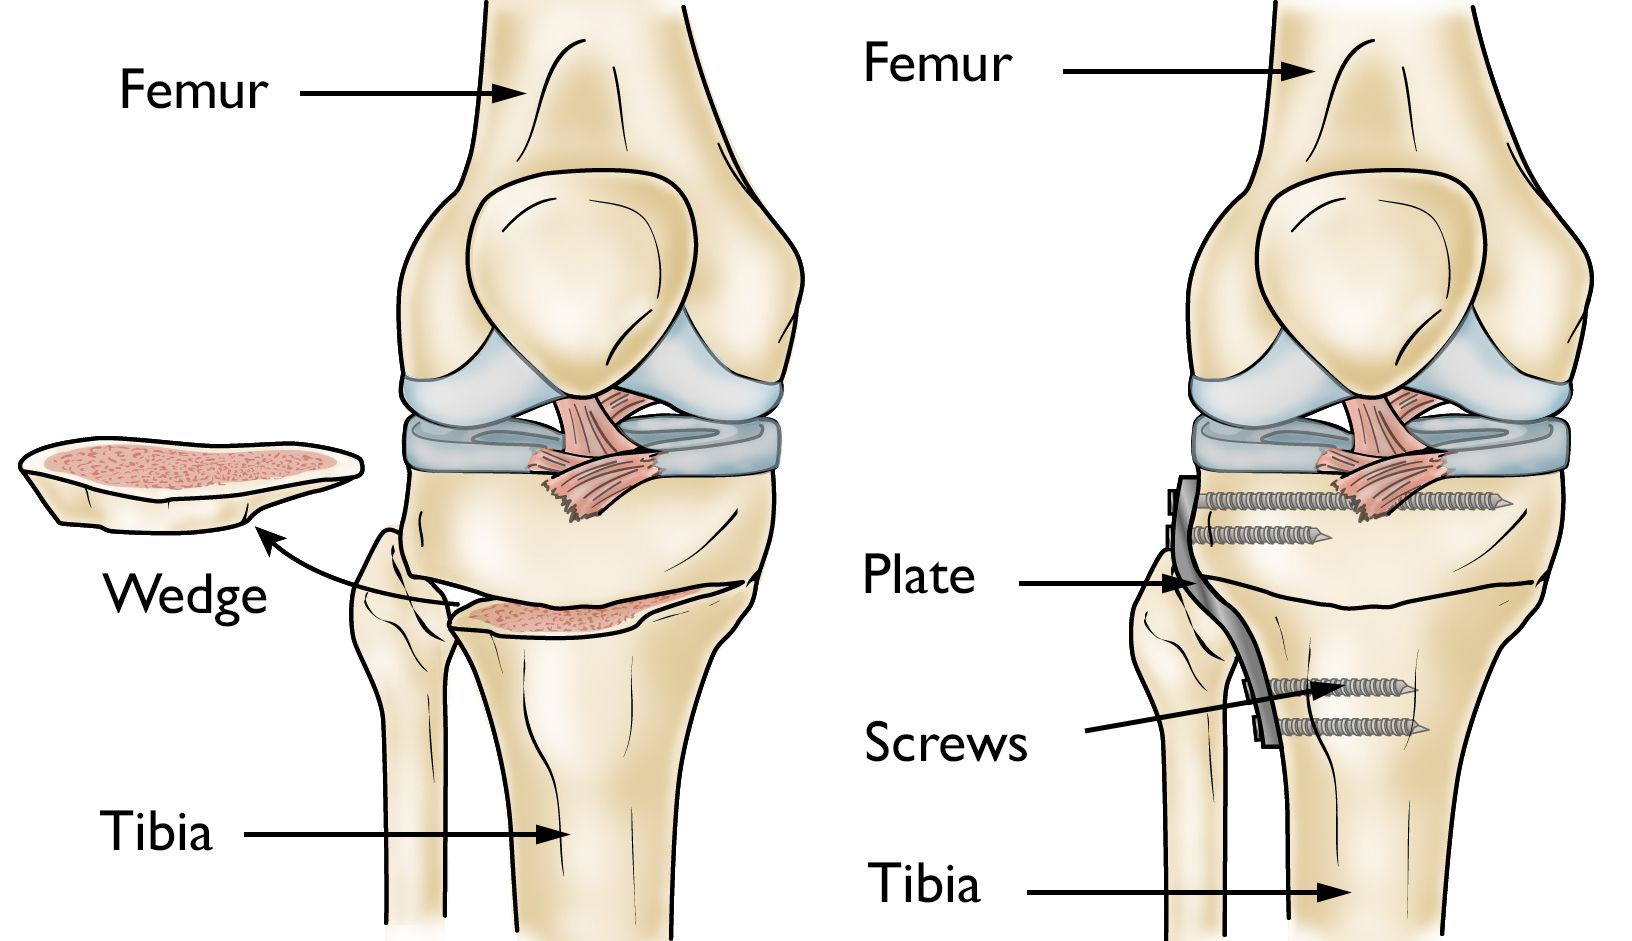

Osteotomy of the knee

Illustrations show a tibial osteotomy to straighten a bowed leg. (Left) A wedge of bone is removed to straighten out the leg. (Right) After the bone is removed, the tibia is held in place with a plate and screws.